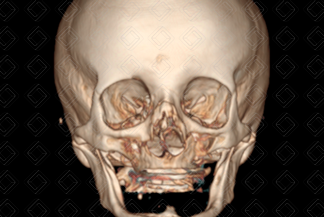

Texto alternativo para a imagem Créditos: Dra. Elazir Mota - Rio de Janeiro/RJ

Descrição das imagens: Tomografia computadorizada da face, cortes axial, coronal e reconstrução 3D. Múltiplas fraturas cominutivas e desalinhadas nos ossos nasais (setas vermelhas na primeira imagem) e septo nasal (seta vermelha na segunda imagem). Observa-se ainda o enfisema de partes moles decorrente do trauma (estrela).